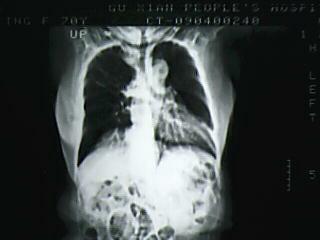

以下是引用bmw011在2009-4-14 19:14:00的发言:[br]右肺继发型肺结核---纵隔淋巴结多发钙化----左肺支扩。支持

以下是引用杀毒软件在2009-4-14 17:52:00的发言:[br]考虑---右肺继发型肺结核---纵隔淋巴结多发钙化----左肺支扩

以下是引用黑白光影在2009-4-14 20:36:00的发言:[br]右肺继发型肺结核;左下慢性支气管炎性病变。